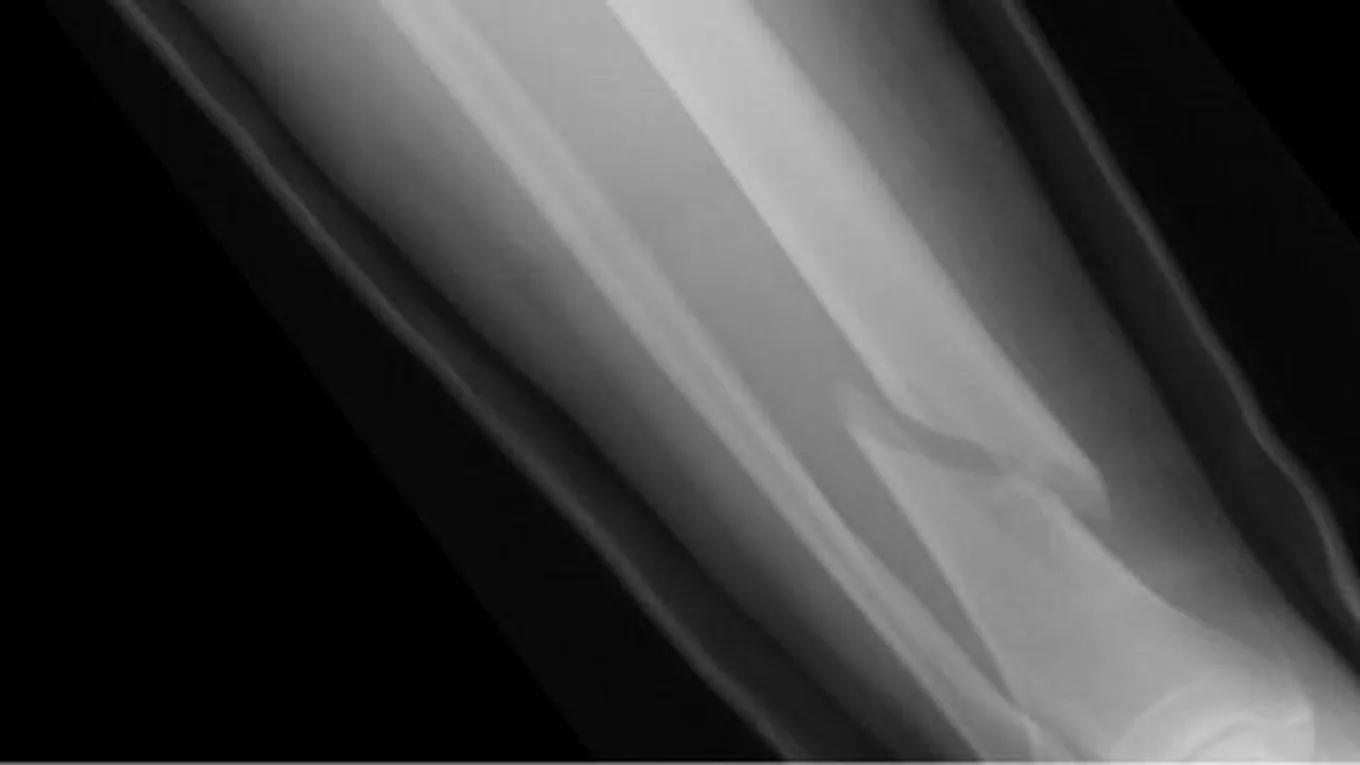

كيف يجبر العظم بسرعة

شفاء كسور العظامكثيراً ما يتعرض المرء لحوادث بسيطة يمكن أن تنجم عنها كسور في مناطق مختلفة في الجسم، ورغم الألم الذي ينجم عن هذه الكسور إلا أنّ وضع الجبيرة

كثيراً ما يتعرض المرء لحوادث بسيطة يمكن أن تنجم عنها كسور في مناطق مختلفة في الجسم، ورغم الألم الذي ينجم عن هذه الكسور إلا أنّ وضع الجبيرة لشفائها يشكل العبء الأكبر على المصاب، فهو مجبر أن ينتظر مدة لا تقل عن ثلاثة أشهر بحسب نوع ودرجة الكسر حتى يفك الجبيرة، وهذا يشكل له ألماً وإزعاجاً في آن واحد، فالجبيرة تجبر المصاب على التقيد بوضع معين في الحركة، والجلوس، والنوم، لذا حتى يتجنب المصاب انتظار كلّ تلك المدة حتى تجبر الكسور التي أصيب بها، لا بدّ له من تناول الغذاء الصحي الذي يحتوي على العناصر الغذائيّة التي تساعد على بناء العظام، وتسرّع شفاءها، والتي سنتحدث عنها في هذا المقال.